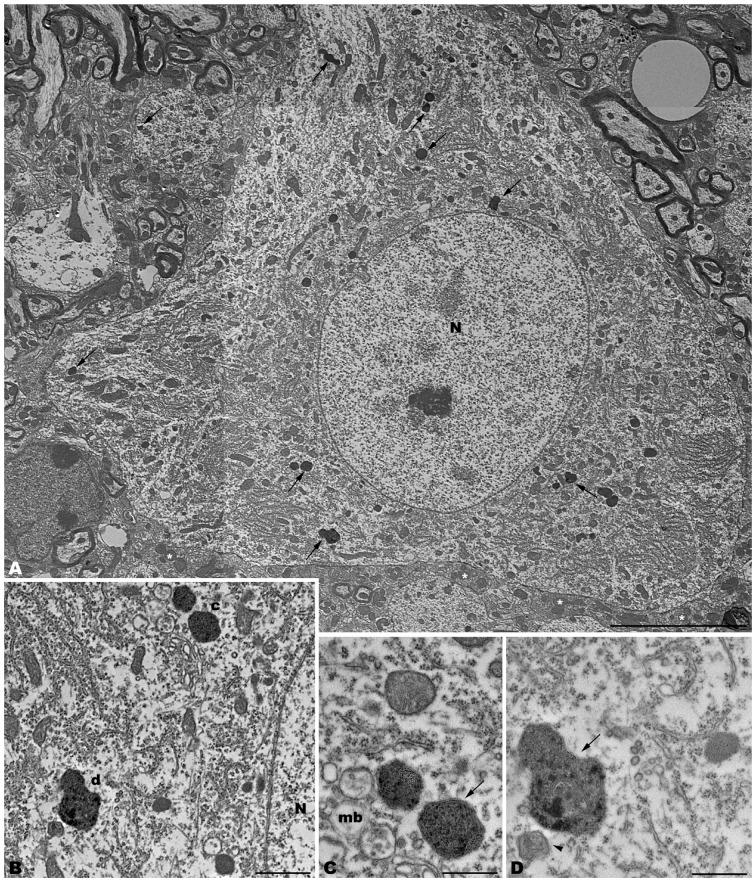

The spontaneous mutation tambaleante is caused by the Gly483Glu substitution in the highly conserved N terminal RCC1-like domain of the HERC1 protein, which leads to the increase of mutated protein levels responsible for cerebellar Purkinje cell death by autophagy. Until now, Purkinje cells have been the only central nervous neurons reported as being targeted by the mutation, and their degeneration elicits an ataxic syndrome in adult mutant mice. However, the ultrastructural analysis performed here demonstrates that signs of autophagy, such as autophagosomes, lysosomes, and altered mitochondria, are present in neocortical pyramidal, CA3 hippocampal pyramidal, and spinal cord motor neurons. The main difference is that the reduction in the number of neurons affected in the tambaleante mutation in the neocortex, the hippocampus, and the spinal cord is not so evident as the dramatic loss of cerebellar Purkinje cells. Interestingly, signs of autophagy are absent in both interneurons and neuroglia cells. Affected neurons have in common that they are projection neurons which receive strong and varied synaptic inputs, and possess the highest degree of neuronal activity. Therefore, because the integrity of the ubiquitin-proteasome system is essential for protein degradation and hence, for normal protein turnover, it could be hypothesized that the deleterious effects of the misrouting of these pathways would depend directly on the neuronal activity.

自发性突变tambaleante是由HERC1蛋白高度保守的N端RCC1样结构域中的Gly483Glu取代引起的,这导致负责通过自噬导致小脑浦肯野细胞死亡的突变蛋白水平增加。到目前为止,浦肯野细胞是唯一被报道为该突变靶向的中枢神经神经元,它们的退化在成年突变小鼠中引发共济失调综合征。然而,此处进行的超微结构分析表明,自噬的迹象,如自噬体、溶酶体和改变的线粒体,存在于新皮质锥体神经元、海马CA3锥体神经元和脊髓运动神经元中。主要区别在于,新皮质、海马和脊髓中受tambaleante突变影响的神经元数量减少并不像小脑浦肯野细胞的急剧损失那么明显。有趣的是,中间神经元和神经胶质细胞中均不存在自噬迹象。受影响的神经元的共同之处在于它们是投射神经元,接受强烈且多样的突触输入,并具有最高程度的神经元活动。因此,由于泛素-蛋白酶体系统的完整性对于蛋白质降解以及正常的蛋白质周转至关重要,所以可以推测这些途径错误导向的有害影响将直接取决于神经元活动。